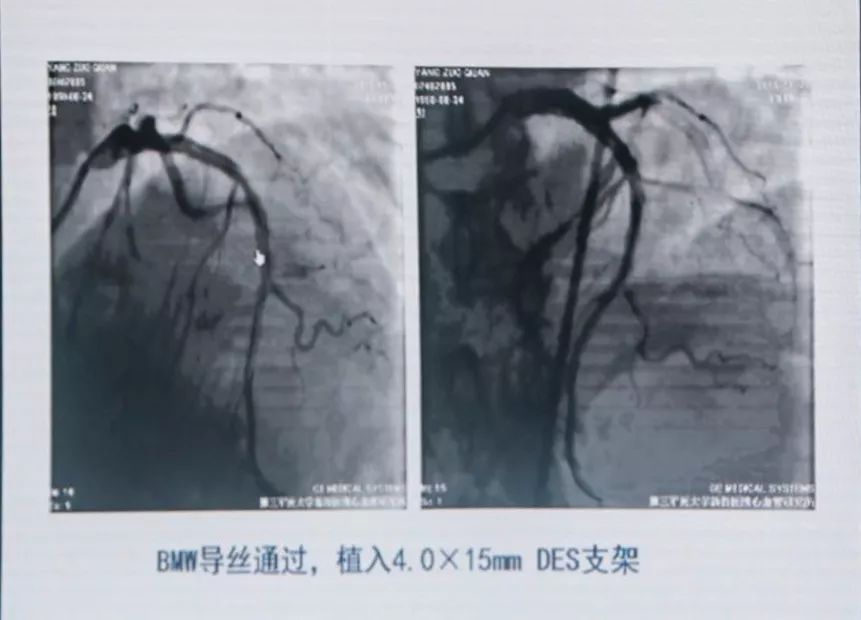

联系陆军军医大学第二附属医院胸痛中心,考虑亚急性支架内血栓形成,绕行急诊,PPCI。

分析血栓形成原因,可能是患者术后自行停用DAPT,支架贴壁不良等。

有条件者应尽快进入导管室行急诊冠状动脉造影,以多体位投照明确无夹层及支架膨胀不良。若血管完全闭塞,待球囊扩张部分血流恢复后再行造影。应尽快使导丝通过血栓病变,建议应用软头导引导丝。

支架内血栓形成可能与支架未充分贴壁有关。可用短于支架长度的高压球囊再次PTCA。若造影确认血栓形成可能与支架近或远端内膜撕裂、支架未完全覆盖病变有关,可再次置入支架,观察20 min后,若患者胸痛缓解、血压及心电监测稳定、TIMI血流III级,可视为成功。但应关注,除非有证据显示血栓形成与上述因素相关,否则不可再次置入新支架。Dutch研究发现,首次出现支架血栓的患者,再次置入新支架,发生支架血栓的风险比未置入新支架的患者增加4.2倍。